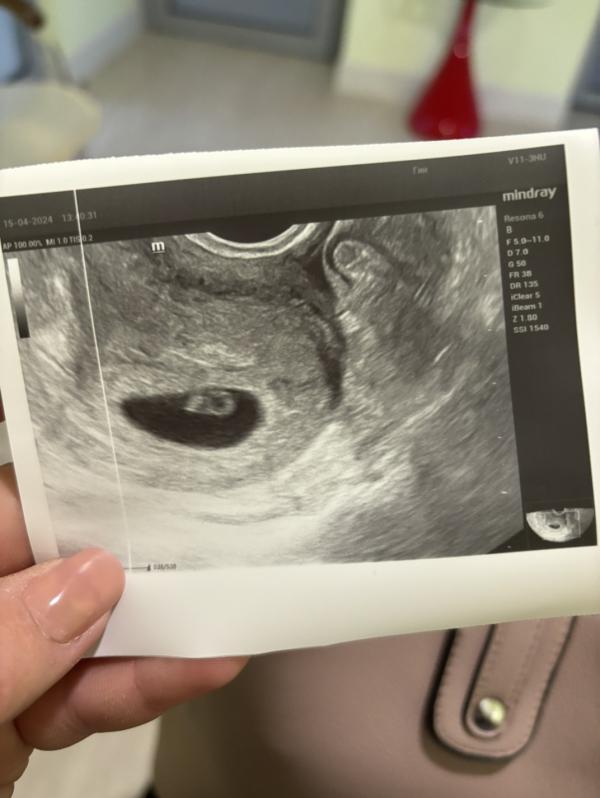

УЗИ показало наше счастье! Как растёт малыш?

Сегодня была на узи всё хорошо, наше маленькое счастье растёт 🥰❤️